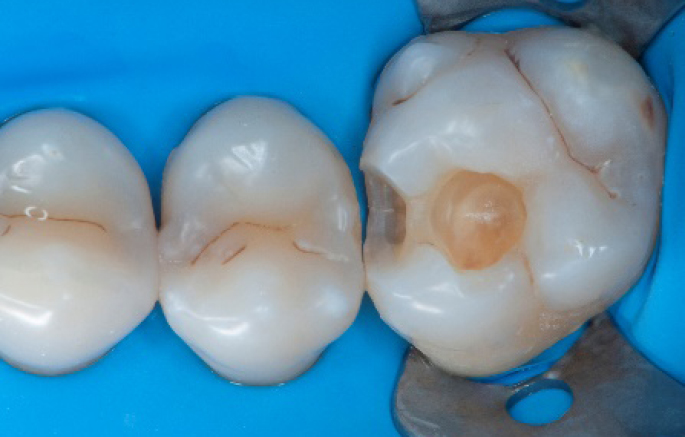

Step 8:

Transformation of class II into class I, restoring the interproximal wall with Spectra ST4 composite in shade A2.

Step 9:

Transformation of a big class I into a small class I, using SDR® flow+ material in one increment up to 4 mm.

Step 10:

The situation after the application of SDR® flow+ material.